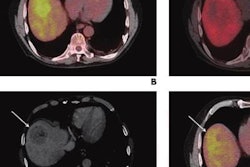

Patients with a common form of liver cancer experienced better treatment outcomes in a recent study when clinicians paired transarterial radioembolization (TARE) with microbubble destruction by ultrasound (US) waves, according to early results published on December 15 in Radiology.

The study is believed to be the first in-human clinical trial evaluating the use of microbubble destruction and TARE to treat hepatocellular carcinoma (HCC). Based on the early findings, the combination looks like a promising method to improve TARE outcomes.

Despite its increasing popularity, TARE is not as effective as clinicians would like. Preclinical research in rodents suggests that using external ultrasound waves to destroy microbubble contrast agents may improve TARE response. The idea is that the energy of the destroyed contrast agents damages the tumor blood vessels, making them more sensitive to the effects of radiation.

The new, preliminary results show that the preclinical research may translate to humans with HCC. In the 28-person study, a significantly greater proportion of patients achieved partial or complete liver tumor response if they received both TARE and ultrasound-triggered microbubble destruction.